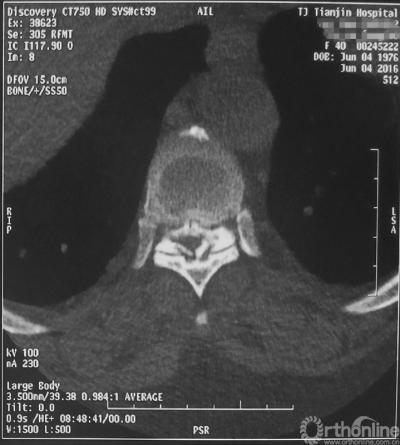

最终,由任万陆主任亲自为患者进行了全身麻醉,苗军主任为其实施了后路的胸8-10椎板减压术,手术麻醉过程平稳,手术出血不多,术后不仅没有截瘫,神经功能进一步恢复,好转出院。术后一个月随访,患者已经可以扶助行器行走,患者对疗效非常满意。

术后CT